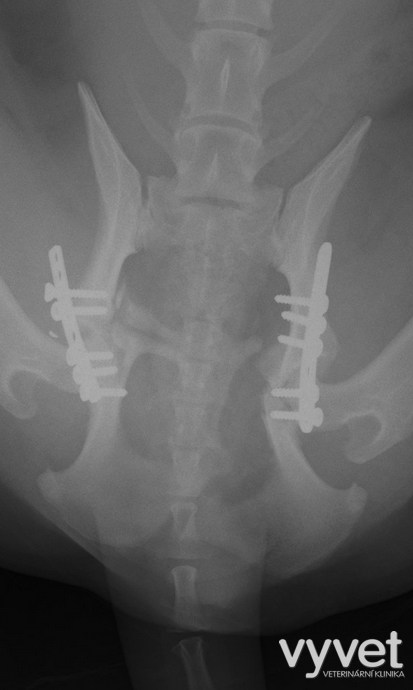

Nejčastějším problémem dlouhých kostí jsou zlomeniny (fraktury)

Rozdělujeme je do několika skupin podle charakteru, množství fragmentů, průběhu linie lomu, dislokace, stability atd.

Je mnoho popsaných metod fixací fraktur. Neinvazivní metodou je přikládání fixačních obvazů a kastů. Tento typ fixace však není ideální, protože nejsme schopni u zvířat zabezpečit dostatečně dlouhou dobu klidu pro srůst kosti. Ideální metodou je invazivnější přístup a to chirurgická repozice s následnou fixací osteosyntetickým materiálem.

Na našem pracovišti používáme zejména ploténky a hřeby.